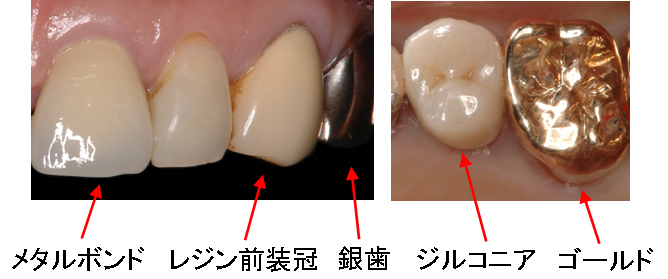

白いかぶせ物には、メタルボンド、ジルコニア、レジン前装冠の3種類があります。

メタルボンドは、セラミックのかぶせ物です。補強のため裏側に金属を使用しています。

ジルコニアは、オールセラミックのかぶせ物・つめ物です。金属を使用していません。

レジン前装冠は、保険適応のプラスチックのかぶせ物です。補強のため裏側に金属を使用しています。